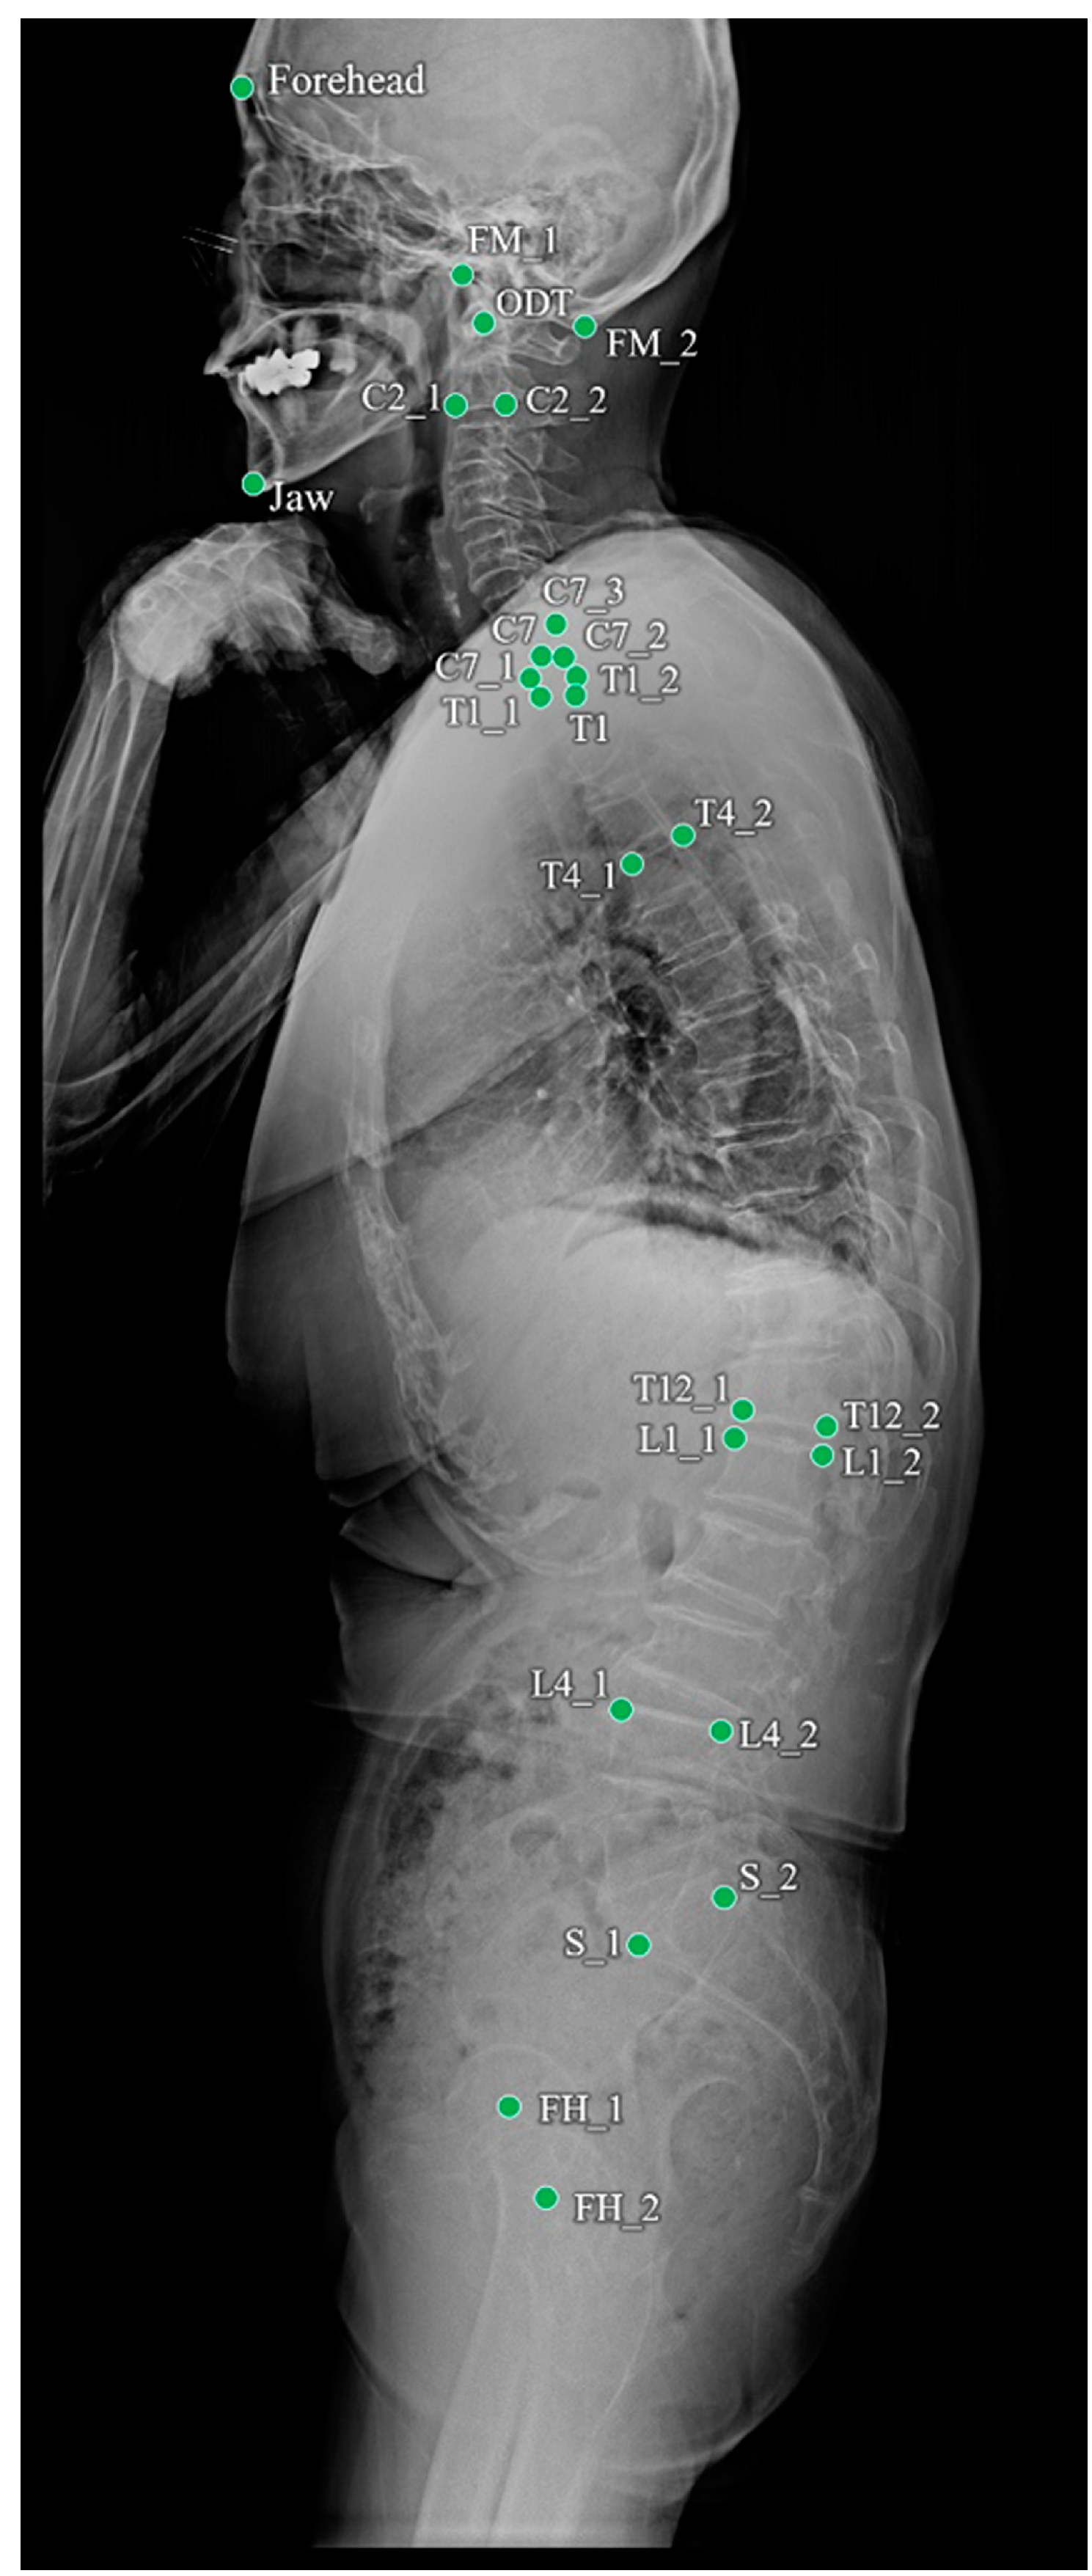

| Name | Description |

|---|---|

| FH_1 | Center of the Femur head |

| FH_2 | Center of the Femur head |

| S_1 | Anterior point of the upper endplate of the sacrum |

| S_2 | Posterior point of the upper endplate of the sacrum |

| L1_1 | Anterior point of the upper endplate of the L1 vertebra |

| L1_2 | Posterior point of the upper endplate of the L1 vertebra |

| L4_1 | Anterior point of the upper endplate of the L4 vertebra |

| L4_2 | Posterior point of the upper endplate of the L4 vertebra |

| T4_1 | Anterior point of the upper endplate of the T4 vertebra |

| T4_2 | Posterior point of the upper endplate of the T4 vertebra |

| T12_1 | Anterior point of the lower endplate of the T12 vertebra |

| T12_2 | Posterior point of the lower endplate of the T12 vertebra |

| T1 | Center of the T1 vertebral body |

| Forehead | Forehead |

| FM_1 | Anterior point of the foramen magnum |

| FM_2 | Posterior point of the foramen magnum |

| ODT | Odontoid |

| Jaw | Jaw |

| C2_1 | Anterior point of the lower endplate of the C2 vertebra |

| C2_2 | Posterior point of the lower endplate of the C2 vertebra |

| C7 | Center of the C7 vertebral body |

| C7_1 | Anterior point of the lower endplate of the C7 vertebra |

| C7_2 | Posterior point of the lower endplate of the C7 vertebra |

| C7_3 | Posterior point of the upper endplate of the C7 vertebra |

| T1_1 | Anterior point of the upper endplate of the T1 vertebra |

| T1_2 | Posterior point of the upper endplate of the T1 vertebra |